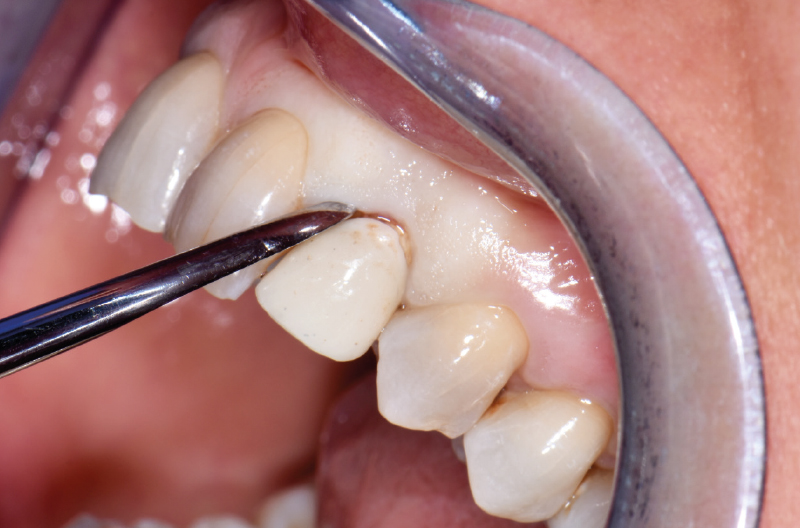

Dopo circa 2 mesi dalla protesizzazione provvisoria si è proceduto alla realizzazione del manufatto protesico con tecnica chair side Sirona con l’ausilio del moncone Ti-Base (Figg. 48-56).

- Fig. 48

- Fig. 49

- Fig. 50

- Fig. 51

- Fig. 52

- Fig. 53

- Fig. 54

- Fig. 55

- Fig. 56